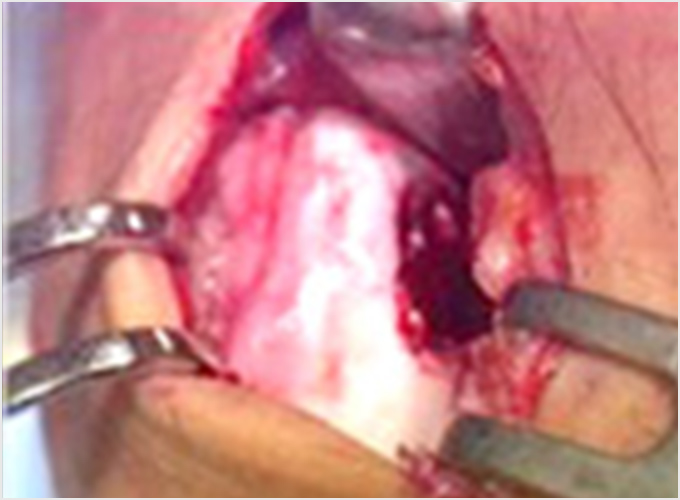

離断性骨軟骨炎(上腕骨小頭障害)

野球肘で最も重症になる障がいの1つです。ひどくなると関節軟骨の一部がはがれて関節ネズミとなったり、肘が変形して動きが悪くなったりします。初期に発見されれば投球禁止で治り、手術はしなくてもすむ場合が多いのですが、末期になると手術が必要となり、手術をしても肘の動きの制限や変形が残ってしまうこともあります。10歳前後で発症することが多いのですが、初期には自覚症状がないことが多く、13-17歳ごろにグラグラになった軟骨がはがれて痛みが出て初めて医療機関を受診されることもよくあります。 手術となった場合には骨の成長の度合い、病変の進行具合、病変の大きさなどにより手術方法が変わります。軟骨が安定している場合には軟骨を固定する手術を行う場合が多いです。軟骨がはがれている場合、病変が小さければ関節鏡を用いてはがれた、あるははがれかけている軟骨を摘出します(図4a)。病変の直径が1㎝以上であれば切開手術で膝の軟骨を病変部に移植します(図4b)。 最近全国各地で少年野球検診が行われるようになりましたが、一番の目的は離断性骨軟骨炎を早期に発見し、重症になる前に治療を行うことなのです。平成28年から多くの医師、理学療法士の協力により名古屋でも行われるようになりました。私も検診に参加し、エコーでのチェックを担当しました。およそ100人に1-2人の割合で発見されました。